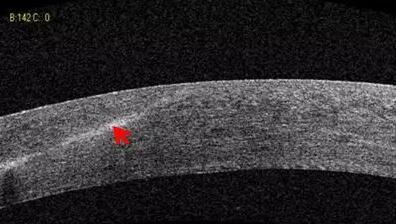

2、角膜厚度评估,角膜水肿、瘢痕、混浊、溃疡、异物、炎症、胬肉等断层观察

3、角膜屈光手术后角膜瓣观察、角膜厚度评估等

4、后弹力层角膜内皮移植术(DSEK)、板层角膜移植术、白内障术后内皮层脱落等术后观察